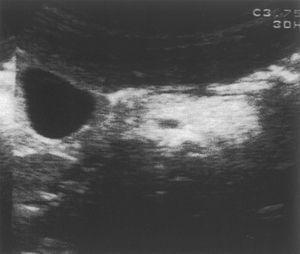

Se le realiza un hemograma y bioquímica básica en la que se objetiva una fórmula leucocitaria con linfocitosis y neutropenia (730/μl), así como una GOT de 110 y una GPT de 124, siendo el resto de parámetros normales. Se descarta hepatopatía por virus hepatotropos más habituales, déficit de a1-antitripsina, enfermedad de Wilson, fibrosis quística, trastornos metabólicos más frecuentes, patología hepática autoinmune, miopatía oculta y enfermedad celíaca. Se solicita una ecografía abdominal (fig. 1) en la que se observa una hepatomegalia homogénea y un aumento de ecogenicidad en páncreas. Ante la sospecha de SDS se solicita una elastasa pancreática: 52 μg/g de heces (insuficiencia grave 6,7), una serie ósea que se informa como normal y una tomografía computarizada abdominal (fig. 2) donde se objetiva una disminución difusa y homogénea de la atenuación del páncreas, que muestra un tamaño en los límites bajos de la normalidad; los hallazgos se relacionan con una infiltración grasa global de la glándula.

Figura 2. Disminución difusa y homogénea de la atenuación del páncreas, que muestran un tamaño en los límites bajos de la normalidad. Los hallazgos se relacionan con una infiltración grasa global de la glándula pancreática.